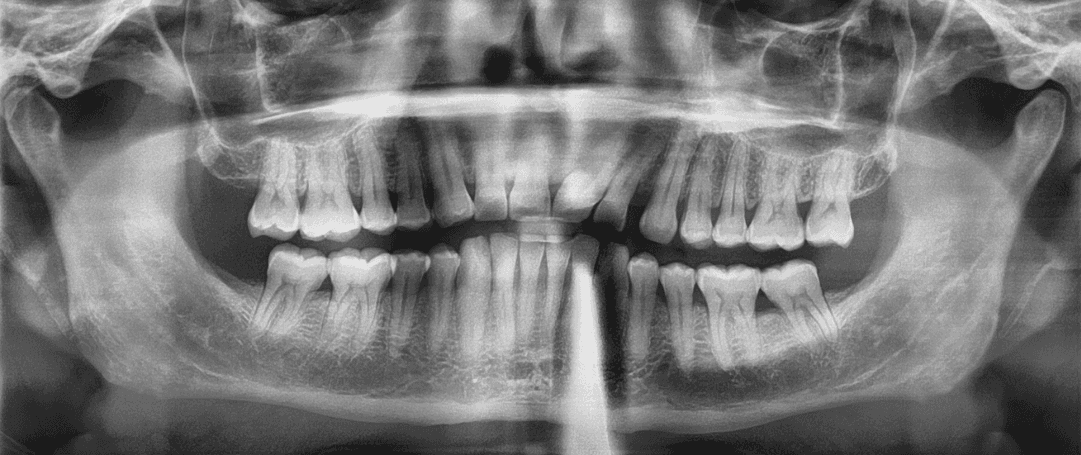

Initial treatment

X-RAYS